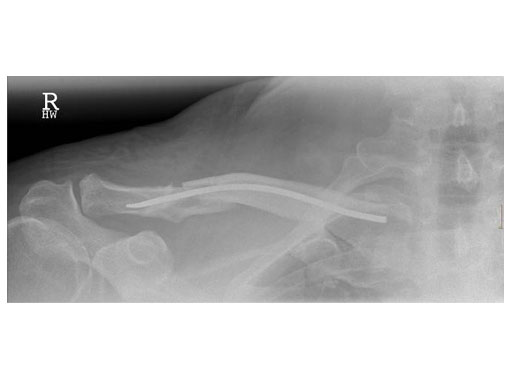

Case 1: Male, 56 years, Bicycle accident

Case 2: 51 years, male, hit by tree